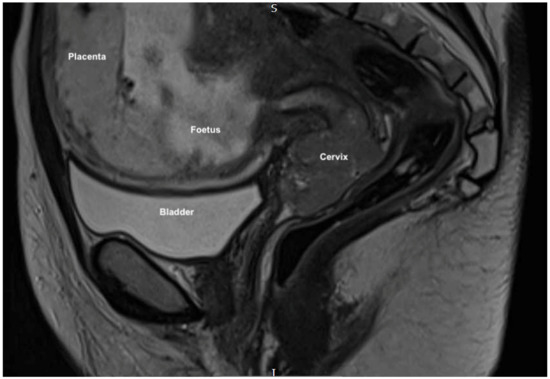

Approach to Radical Hysterectomy for Cervical Cancer in Pregnancy: Surgical Pathway and Ethical Considerations

by Rocco Guerrisi, Sarah Louise Smyth, Lamiese Ismail, Amanda Horne, Federico Ferrari and Hooman Soleymani majd

J. Clin. Med. 2022, 11(24), 7352; https://doi.org/10.3390/jcm11247352 - 10 Dec 2022

Introduction. Cervical cancer is currently the fourth most common cancer in women and in the poorest countries this neoplasia still represents a widespread and potentially lethal disease. We present a rare case of cervical cancer in pregnancy, analyzing the historical changes behind the procedure of radical hysterectomy for cervical cancer and discussing variations in surgical techniques and anatomical definitions that have since been proposed. Results. We present the case of a 33-year-old patient who attended with vaginal bleeding in the second trimester of pregnancy. Examination revealed an abnormal looking cervix, with investigations concluding stage IIb squamous cell carcinoma. Following extensive discussion regarding management options, the patient went on to have a peripartum foetocidal type III nerve sparing radical Wertheim hysterectomy at 18 weeks gestation with conservation and transposition of the ovaries above the level of the pelvic brim. The patient recovered well without significant morbidity and received further input from fertility and psychological medical teams in addition to adjuvant treatment within the department of clinical oncology. Discussion. This case represents several elements of great interest and learning. Notably, we highlight this both due to the surgical challenges that a gravid uterus presents in the execution of a radical hysterectomy; and regarding the compassionate care demonstrated by the team - not only in supporting the patient and her partner in a period of profound turmoil in terms of the management of their cancer diagnosis and unborn child, but also regarding the uncertainty in consideration of the oncological and fertility related outcomes. Conclusion. This manuscript adds to the growing literature on the appropriate use of radical surgery for cervical cancer, more specifically during pregnancy and in consideration of such ethical dilemma, where management guidelines do not exist to aid clinicians further in their provision of treatment. Full article